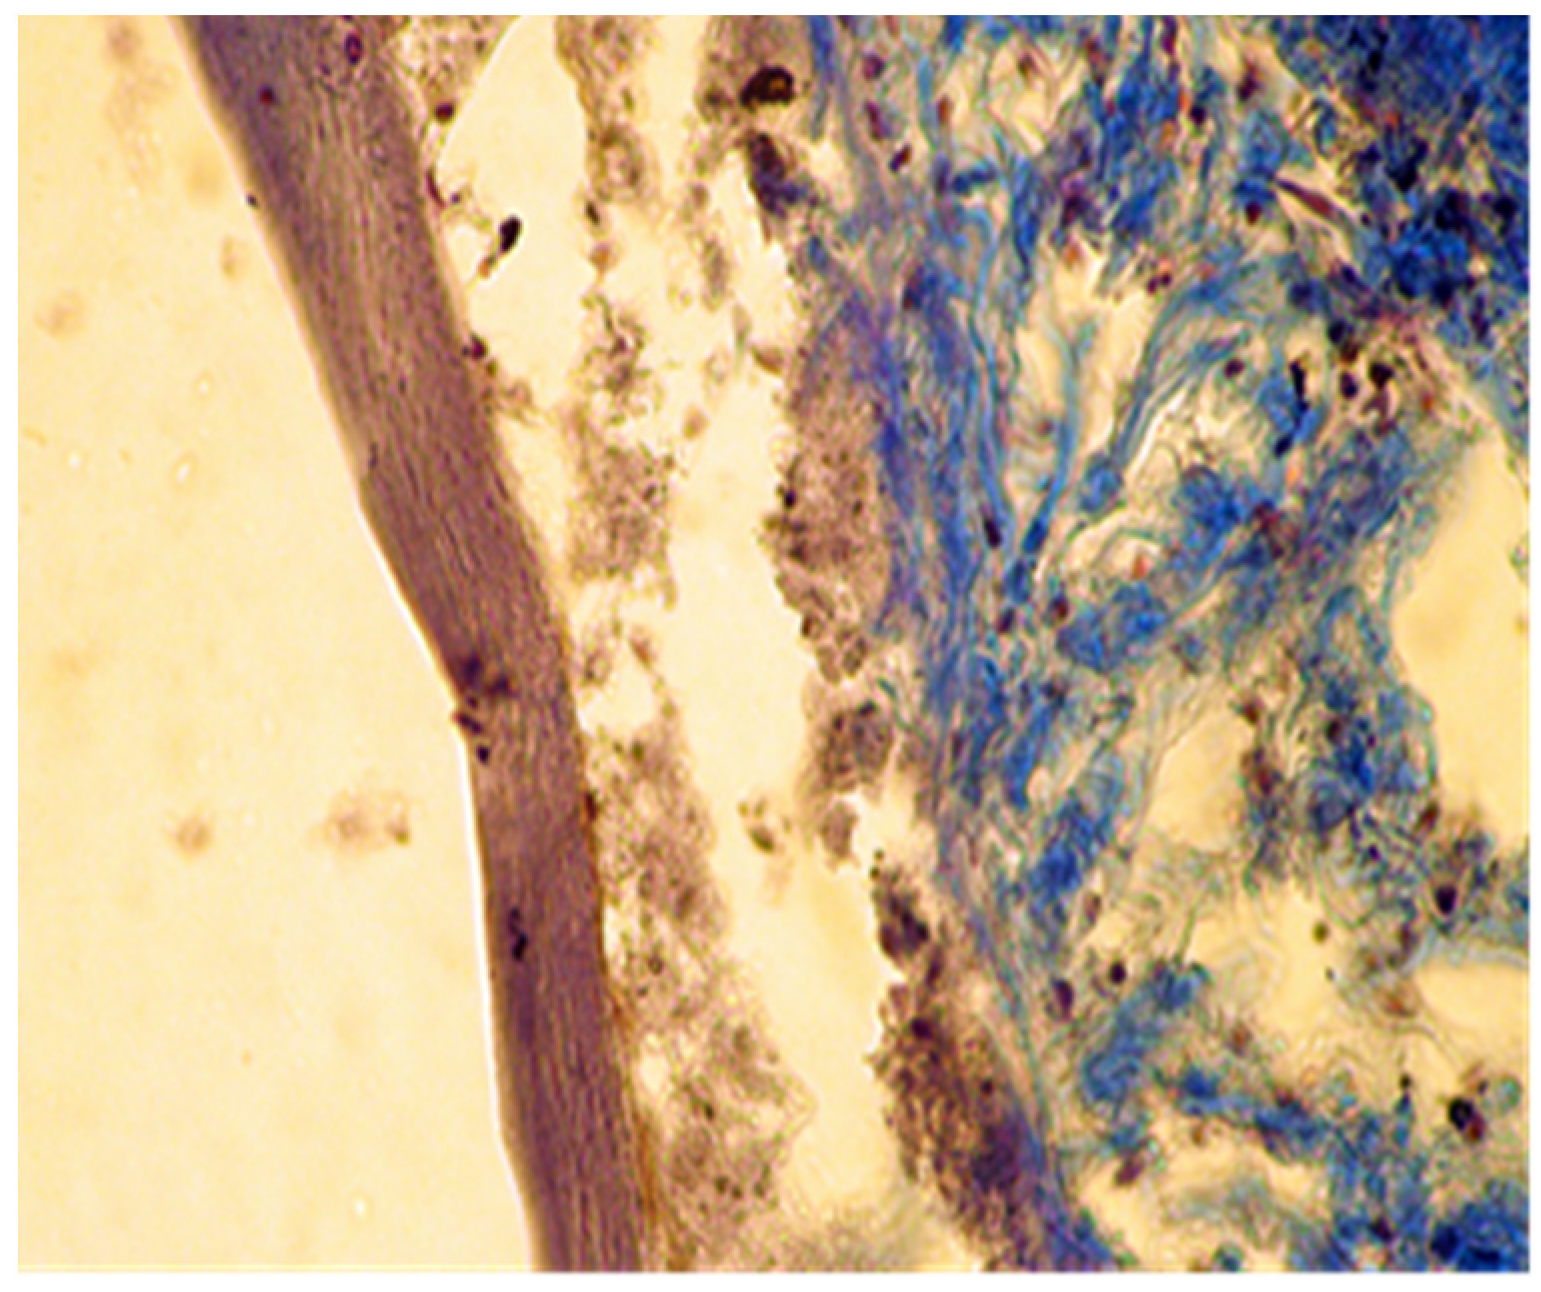

The implanted material was partially reabsorbed. Local mineralization, probably due to the diffusion of released calcium ions from the implant material, was seen in some muscle fibers of the skin (Figure 6).

Figure 6. Calcification of muscular fibers from the skin. Col. Trichrome Masson, ×200.